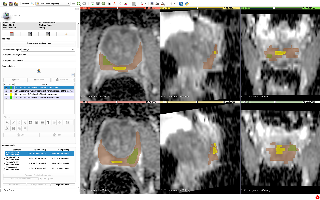

MMWHS

| 名称 | 标注内容 | 类型 | 模态 | 数量 | 标签格式 | 文件格式 |

|---|---|---|---|---|---|---|

| MMWHS | 心脏 | 分割 | CT / MRI | 20CT、20MRI | 类别 | nii |

mmwhs是心脏分割数据集,共有8类,MRI和CT两种模态 相关项目: Hybrid Loss Guided Convolutional Networks for Whole Heart Parsing